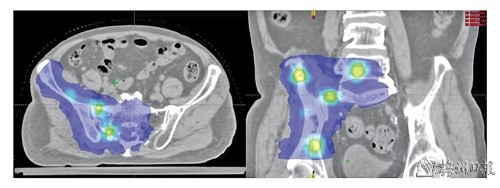

通过智能技术将辐射分割为高、低剂量交替的“攻击网格”。

“空间分割放疗”技术是一种复杂而先进的治疗手段,通过智能技术,将放射量分割为高、低剂量交替的“攻击网格”,高剂量区精准覆盖肿瘤核心,低剂量区巧妙避开脊髓、神经、肠道等要害部位。这种技术既能够强力摧毁癌细胞,又能够为正常组织撑起足够的保护屏障。